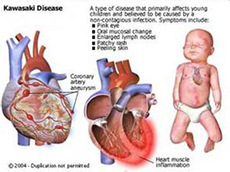

新生儿持续肺动脉高压(PPHN)

疾病介绍:新生儿持续肺动脉高压是由多种病因引起的新生儿出生后肺循环压力和阻力持续增高,而发生心内水平(通过卵圆孔)和(或)动脉导管水平的右向左或双向分流,…【详细】